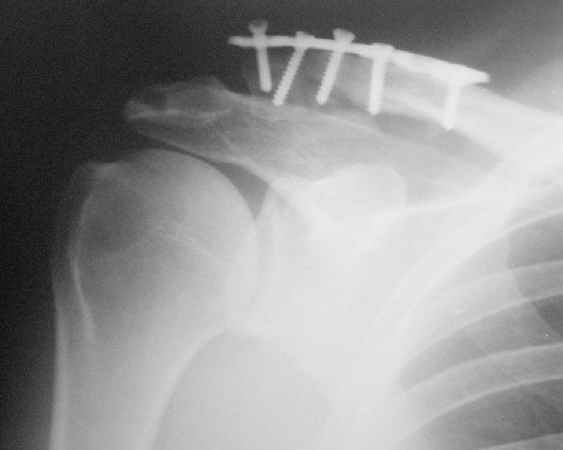

Прошел месяц после остеосинтеза ключицы.

Жалоб больной не предъявляет, работает (предприниматель). Движения в плечевом суставе практически восстановлены. На контрольной R-гр.-положение отломков не изменилось, миграция дистального винта. Следующий осмотр- через месяц.